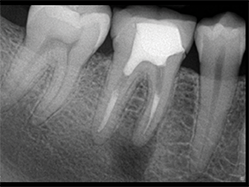

Slika 7: Neuspešan tretman kanala korena sa apikalnom infekcijom i internom resorpcijom u apikalnom delu.

Slika 8: Kontrolna slika pokazuje brzo zarastanje i apikalne regije i resorptivne lezije.

Slučaj neuspešnog tretmana korenskog kanala sa apikalnom infekcijom i unutrašnjom resorpcijom u predelu apeksa prikazuje slika iznad (Slika 7). Nakon uklanjanja prethodnog punjenja, izvršena je hemijska priprema, uz pomoc parcijalnog vakuuma unutar sistema hemikalije su mogle očistiti područje resorpcije bez agresivnog dejstva na periodontalni ligament; ovo je dovelo do zaista trodimenzionalne obturacije sistema kanala.

Slika nakon 4 meseca potvrdjuje brzo zarastanje i apikalne regije i područje resorptivne lezije.